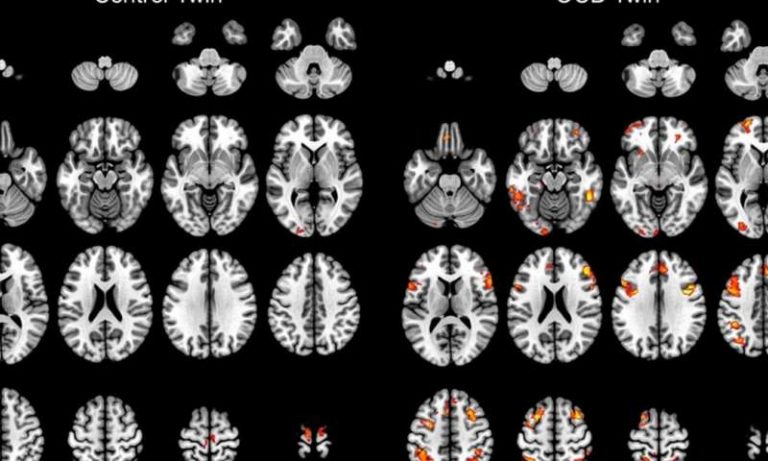

Does living at a higher altitude affect your mental health? VAndreas/shutterstock.com By Dr. Hoehun Ha / 11.05.2017 Assistant...